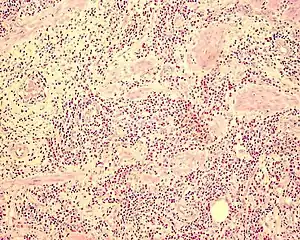

- Demonstração histológica de infiltração eosinofílica em uma ou mais áreas gastro-intestinais ou presença eosinofílica alta em fluido ascítico

Diagnóstico definitivo envolve evidência histológica de infiltração eosinofílica na biópsia. Eventualmente biópsia laparoscópica transmural pode ser necessária.